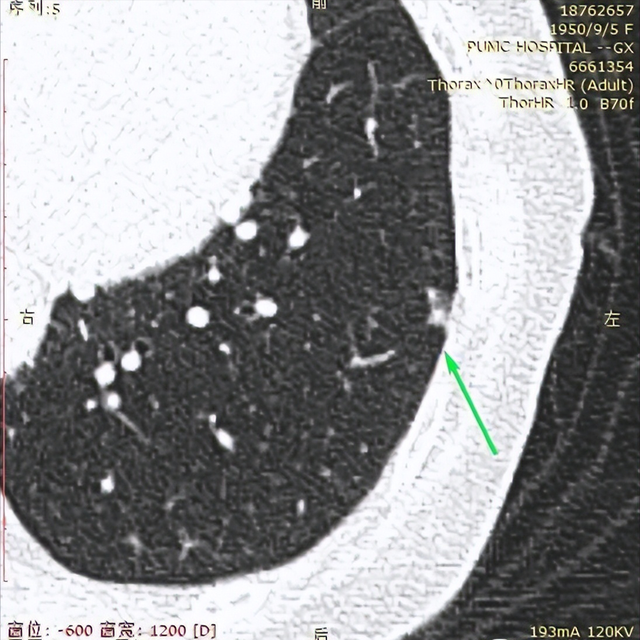

2023年11月1日我在北京也有高分辨CT的医院复查了CT。CT报告单写:双肺多发结节(省略)较大者(3im左52)长径约7mm。看主任助手帮我截图中右侧这2个结节的位置是新发吗?原右肺下叶7mm的结节我没看到。

2023年5月6日我在新桥做的CT,左肺上叶有2个1cm多大小的结节,2023年11月1日CT报告中没有描述这2个大结节,但在图像117/361和图像118/361的两张截图的上方这2个结节影还是可见。

这些情况让我很迷糊!很担忧!烦请主任帮看看我左肺在什么位置有多少个高危结节?到了什么程度?需什么时候手术?能一网打尽吗?右肺是有新发结节吗?是否有需尽快处理的结节?